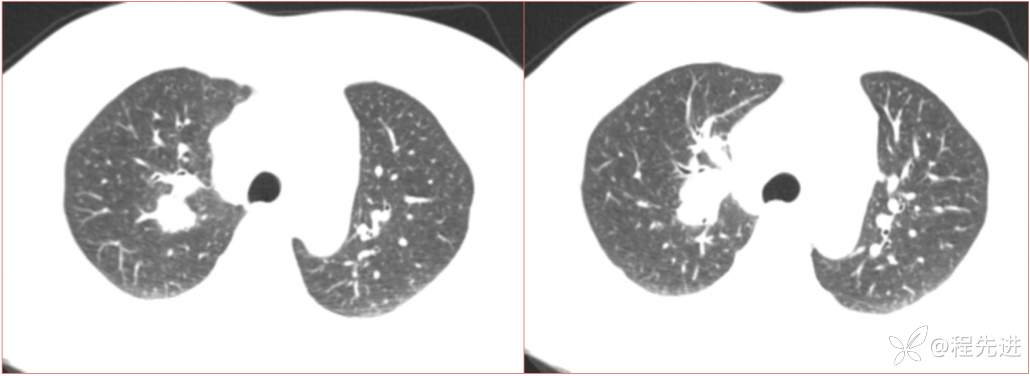

简要病史:患者一周前无明显诱因出现阵发性刺激性咳嗽,咳少量白色粘液痰,咳嗽无明显昼夜节律性,无发热、畏冷、寒战,无头痛、胸闷、胸痛,自行服药后 (具体不详) 症状无缓解,3天前外院胸片检查示右上病变

辅助检查:肺肿瘤标志物:神经元特异性烯醇化酶(NSE):35.72ng/ml(参考值0-16.3);非小细胞肺癌相关抗原211、胚抗原糖类抗原125、铁蛋白、鳞状细胞癌抗原未见异常